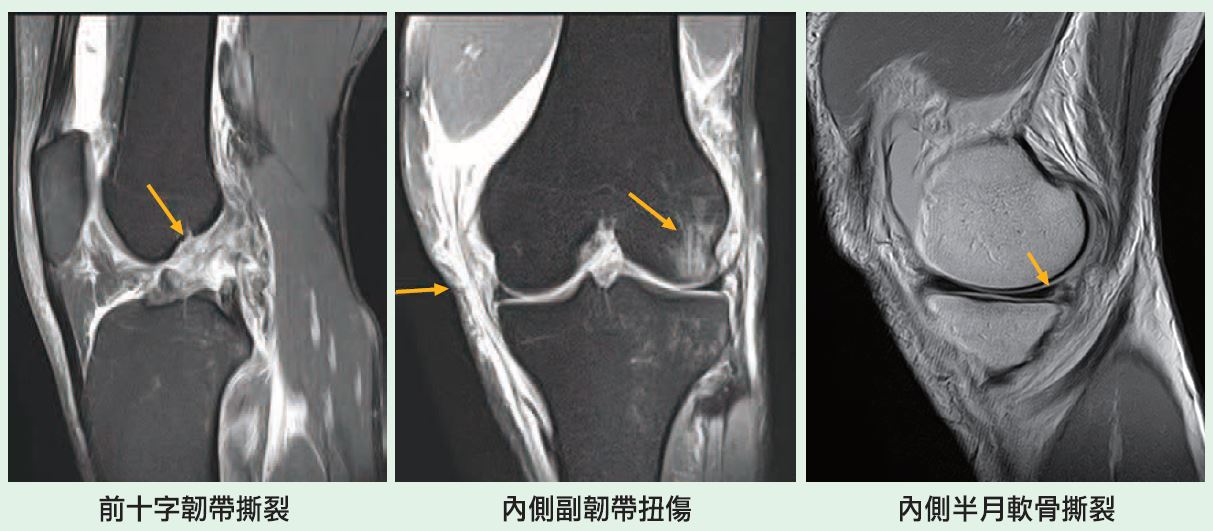

Mriでは前十字靭帯の損傷を高い精度で確認できると同時に、診察では見つけにくい半月板損傷や軟骨損傷を調べることができます(図1)。 図11)mri:膝前十字靭帯損傷 図12)mri:半月板損傷 診察肩関節mriの正常解剖(斜冠状断像) 肩関節mriの正常解剖(矢状断像) 胸部ct(肺野条件) 胸部ct(縦隔条件O脚傾向の人が多いので膝の内側の軟骨がすり減る場合が多いとされています。欧米人では外側型もあり、お皿の骨(膝蓋骨)の軟骨が摩耗する型もあり、各型混在しています。 発生要因 日々の関節の摩耗による場合と、半月板や靭帯損傷後に関節変化が出る場合があります。 肥満者のほうが

膝關節半月板病變的mri 診斷與鑑別

膝關節主要韌帶損傷的mri 診斷 一 人人焦點